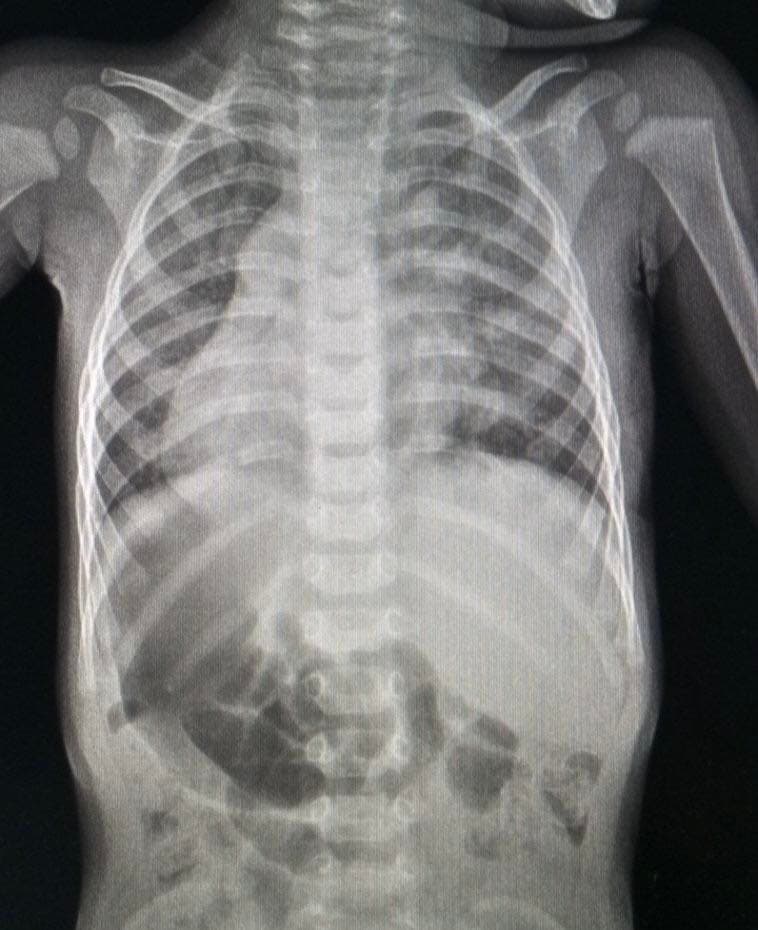

За словами медиків, Дем’янчик має рідкісну анатомічну особливість — усі його органи розташовані навпаки: серце, селезінка і підшлункова — справа, а печінка та апендикс — зліва. Такий стан трапляється вкрай рідко, але зазвичай не впливає на якість життя.

Втім, у дев’ять місяців під час планового огляду лікарі почули шуми у серці. Обстеження показало дефект міжпередсердної перегородки з частковим аномальним дренажем легеневих вен — судини впадали не в ліве передсердя, як має бути, а в праве. Через дзеркальну анатомію це ще більше ускладнювало ситуацію.